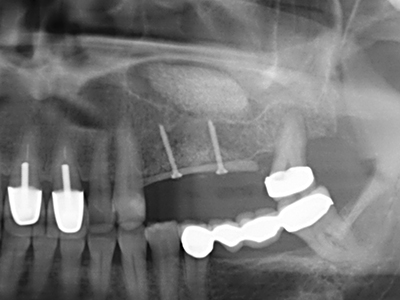

Indication: Apical resection

When surgical procedures are performed on bone in the immediate vicinity of sensitive structures such as blood vessels or nerves, rotary instruments pose a significant risk of iatrogenic injury. Piezoelectric devices can be helpful for preparation of bone covers and removal of hard tissue close to nerves, particularly for exposure of nerves after iatrogenic injury but also during nerve lateralization for resective and reconstructive procedures or implant placement (Fig. 17-20). Light contact between the piezotip and the nerve does not generally result in damage but proceeding incautiously with saw-like motions or attachments where a residual bone substrate remains may cause temporary or even permanent nerve damage. However, the risk of damage is considered to be substantially lower than when using saws or milling instruments (Pereira, Gealh et al. 2014).